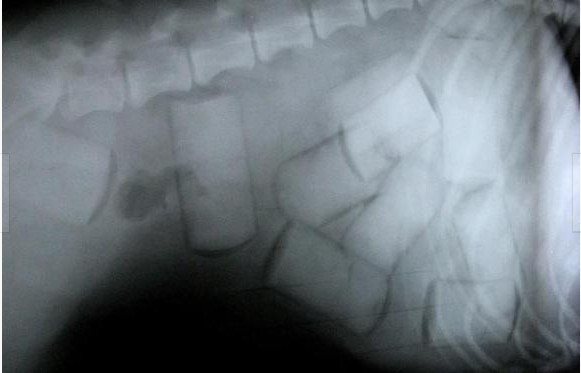

本文摘要:揭秘 贩毒分子 的藏毒新 招数 无奇不有(图) 一只拉布拉多犬被送到欧洲之前,一个哥伦比亚兽医把毒品放入它的体内,图为拉布拉多犬的X光照片显示,其胃部和胃粘膜之间藏有许多小包装的可卡因。

一只拉布拉多犬被送到欧洲之前,一个哥伦比亚兽医把毒品放入它的体内,图为拉布拉多犬的X光照片显示,其胃部和胃粘膜之间藏有许多小包装的可卡因。 (责任编辑:admin)